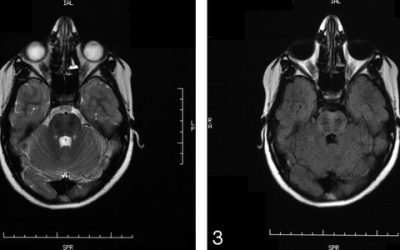

Células madre del propio paciente para curar la Enfermedad de Machado-Joseph

Células madre del propio paciente para curar la Enfermedad de Machado-Joseph Hereditaria y neurodegenerativa, esta patología sin cura hasta el momento provoca atrofias musculares y descoordinación motora. Fuente, 03/08/2016 Células madre del paciente para curar la...